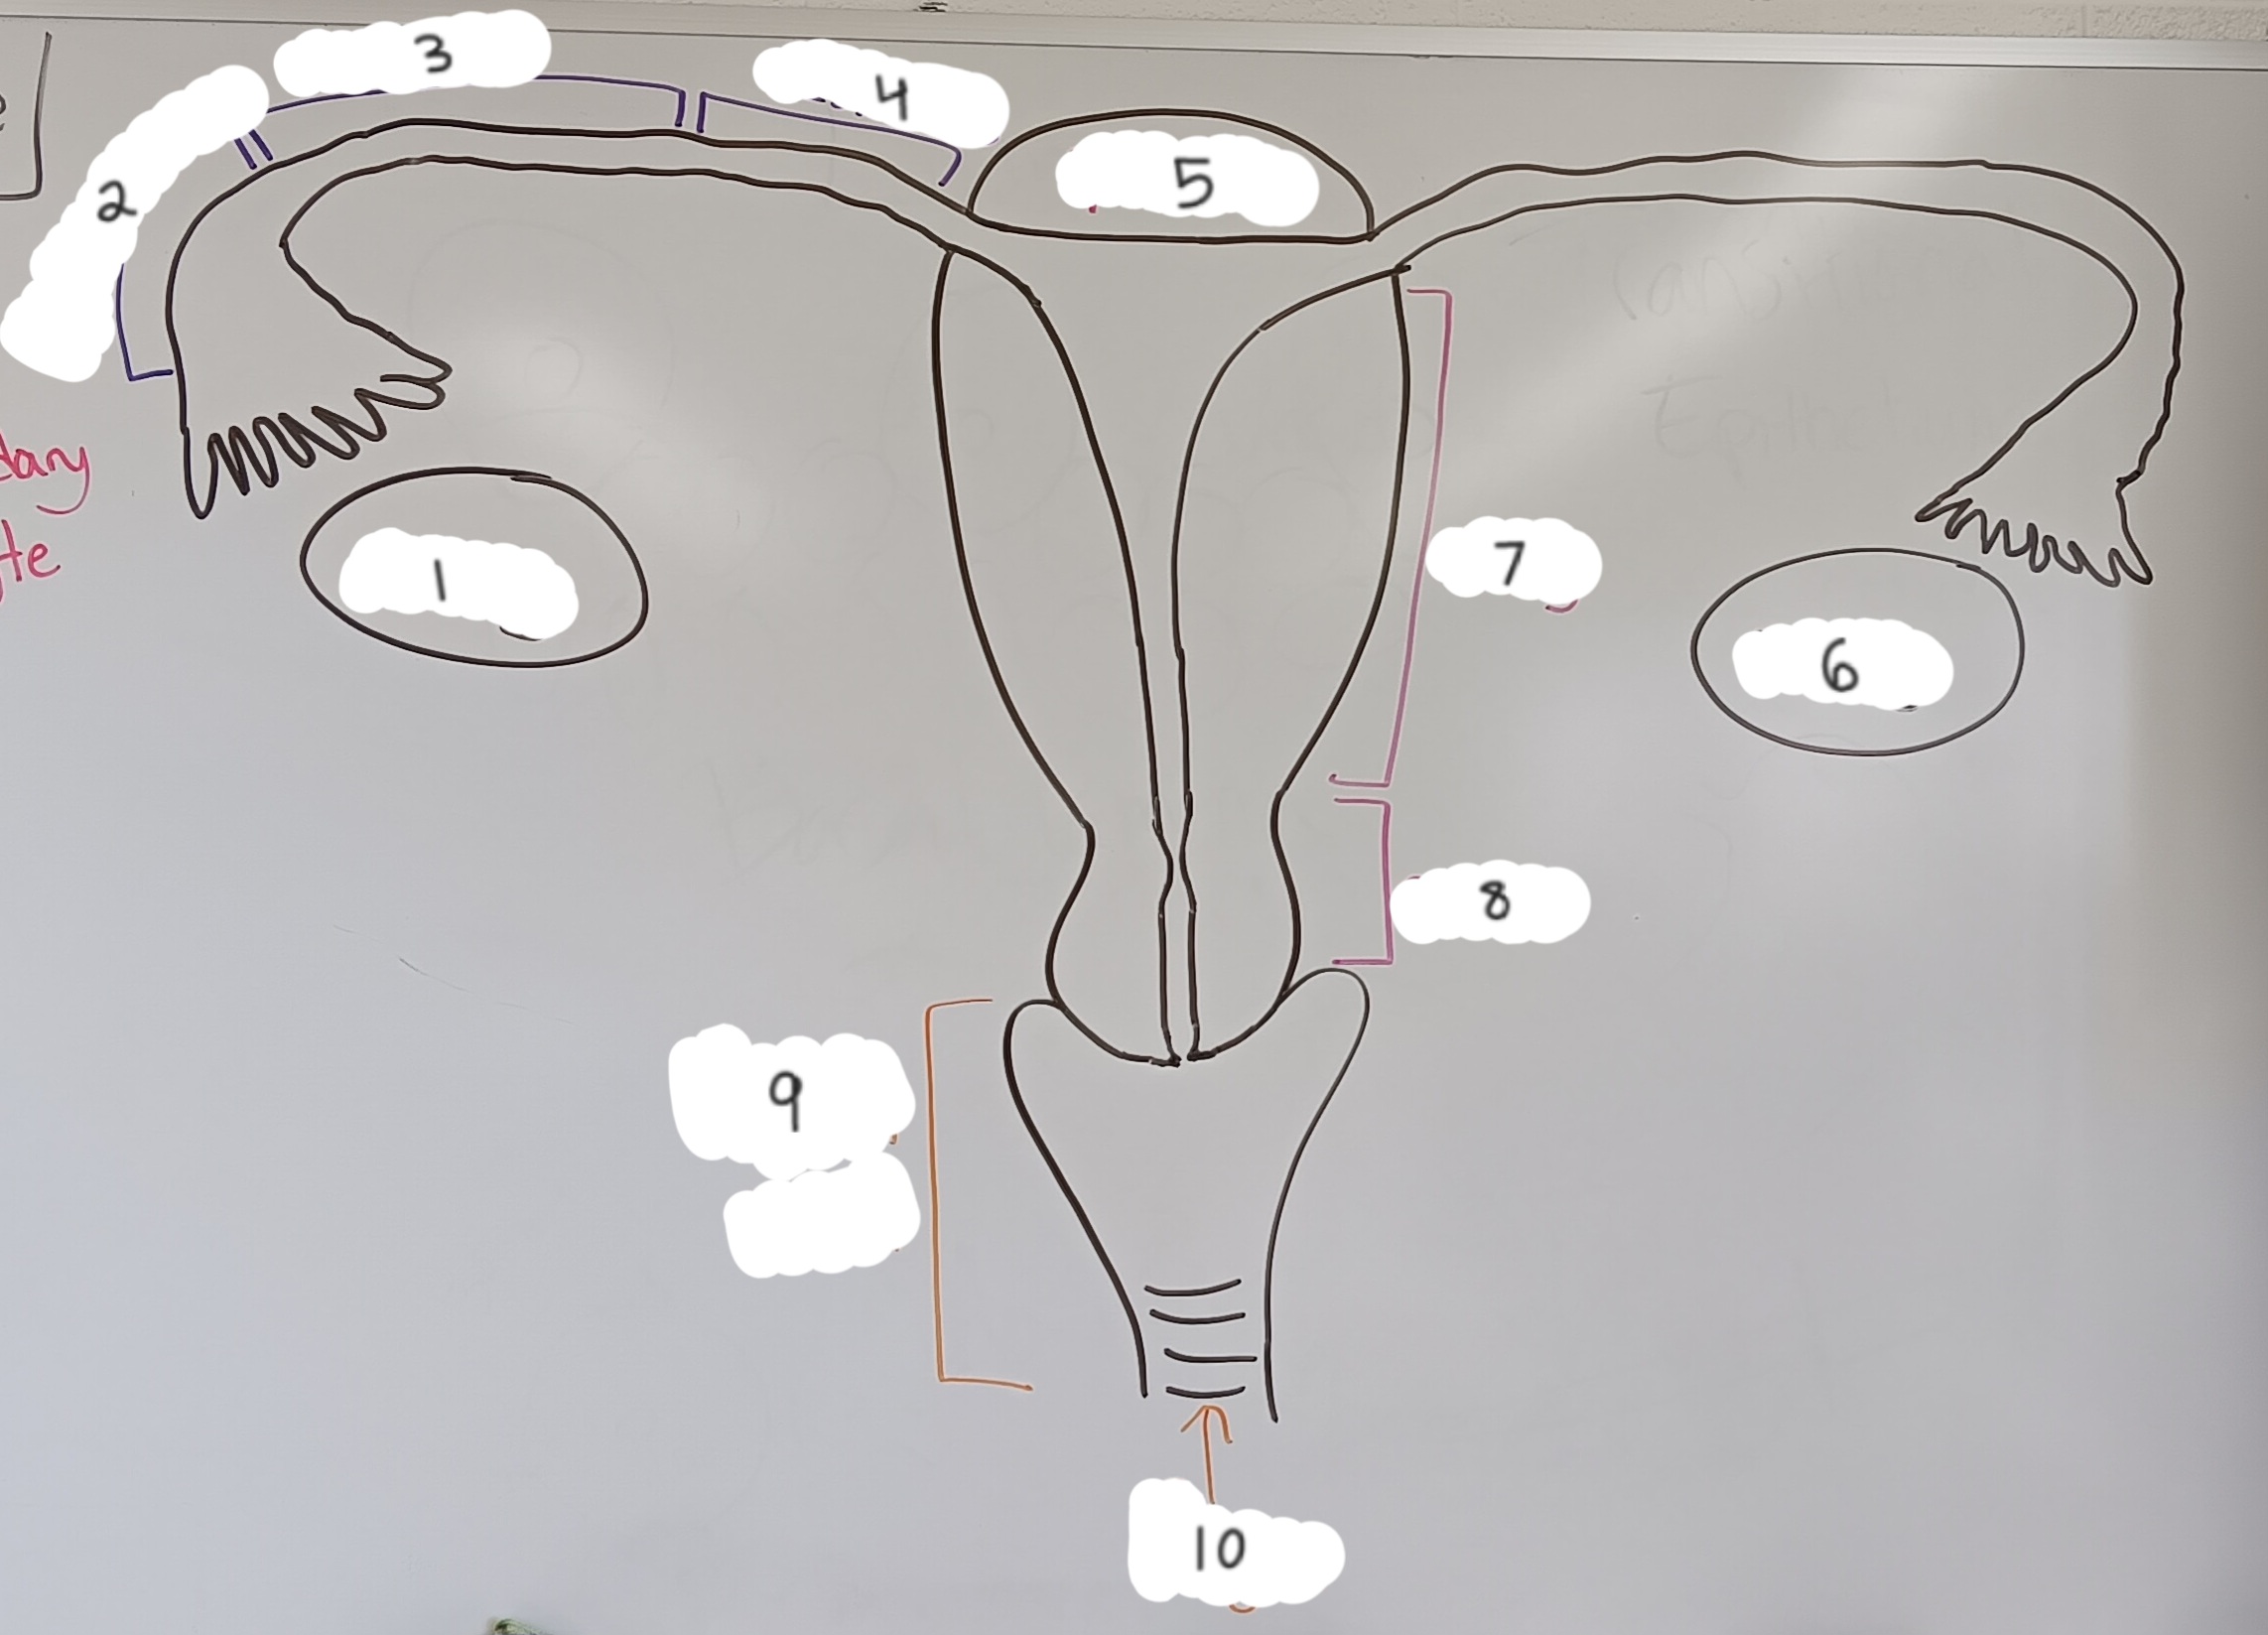

right ovary

1 (lt or rt)

infundibulum

2

ampulla

3

isthmus

4

fundus

5